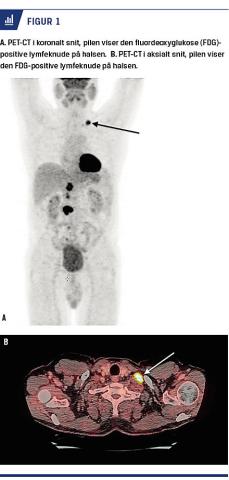

En 57-årig mand blev henvist fra en mave-tarm-kirurgisk afdeling til en øre-næse-hals-afdeling i et nyt kræftpakkeforløb pga. en mulig metastase på halsen. Han var året forinden blevet opereret for en cancer coli. På en planlagt kontrol-CT blev der fundet en hævet lymfeknude retroperitonealt. Denne var utilgængelig for bioptering. Ved en efterfølgende PET lyste den pågældende lymfeknude op sammen med en lymfeknude supraklavikulært på venstre side af halsen (Figur 1). Der blev foretaget grovnålsbiopsi af lymfeknuden på halsen, hvorved man fandt en karcinommetastase uden relation til patientens tidligere cancer coli (som var et adenokarcinom). Der blev ikke farvet for p16. Lymfeknuden blev herefter eksstirperet i generel anæstesi på øre-næse-hals-afdelingen. Patologisvaret viste metastatisk seminom. Patienten blev i et nyt kræftpakkeforløb henvist til en urologisk afdeling. Ved ultralydskanning af testiklerne blev der fundet et velafgrænset ekkofattigt suspekt område i højre testikel. Venstre testikel blev fundet normal. Patienten blev højresidigt skrotaleksploreret, og der blev biopteret fra området. Frysesvarshistologien viste malignitet, hvorfor han fik foretaget højresidig orkiektomi i samme procedure. Det endelige patologisvar viste et burned-out seminom. Han blev herefter henvist til onkologisk efterbehandling og opfølgning.